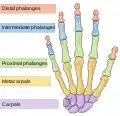

Les métacarpiens (ou os métacarpiens ou os du métacarpe) sont les os formant le métacarpe squelette de la paume de la main. Ils sont articulés dans leur partie supérieure[1] avec les os de la rangée distale du carpe et se prolonge au niveau de sa partie inférieure[1] par les phalanges proximales. Ces os sont unis par les muscles interosseux.

Les métacarpiens sont cinq petits os longs numérotés de 1 à 5, de dehors en dedans en position anatomique : 1 correspond au pouce et 5 à l'auriculaire. Chacun se compose d'une base proximale, d'un corps et d'une tête distale.

Vue dorsale des os de la main et des insertions musculaires (les métacarpiens en jaune). Les os du métacarpe sont reliés au poignet par le carpe

Les os du métacarpe sont reliés au poignet par le carpe Os métacarpiens, vue médiale